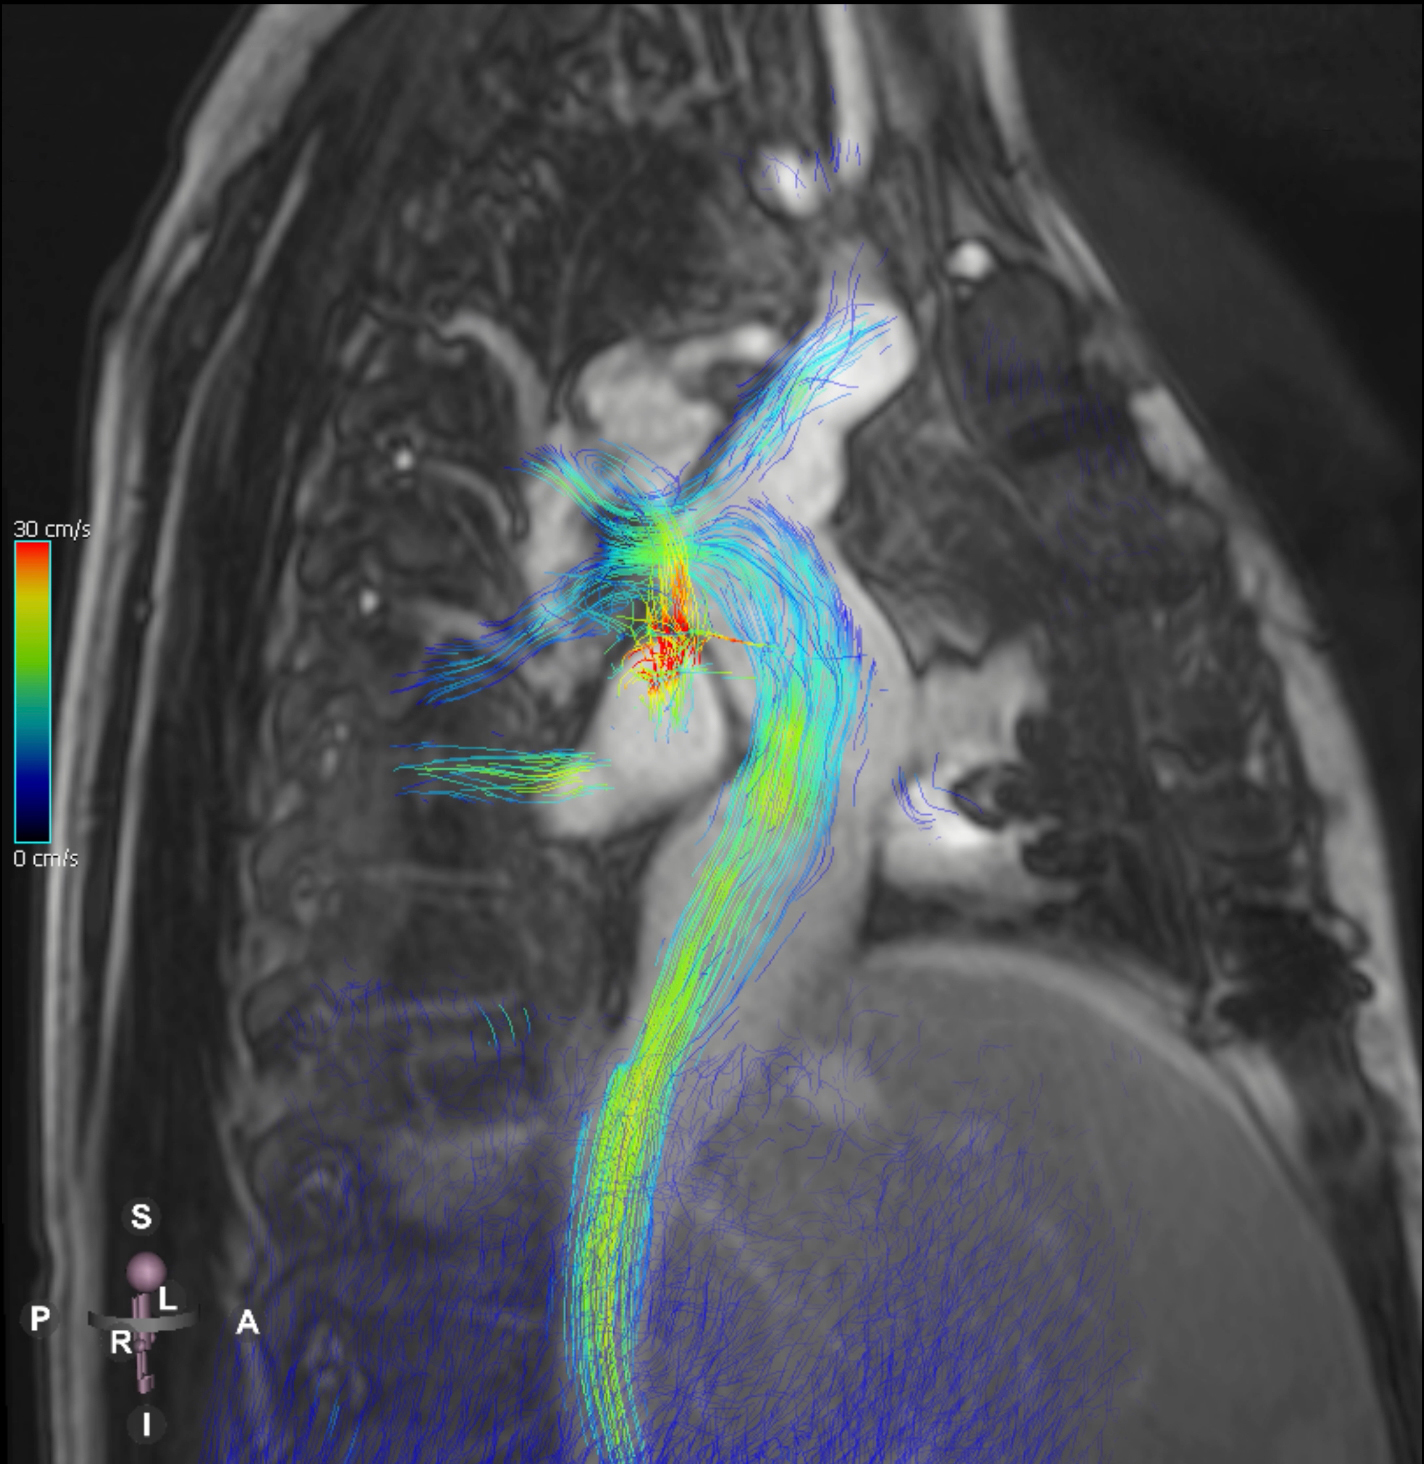

Figure 2. T2-weighted SPACE magnetic resonance demonstrating type 3 lymphatic circulation pattern.